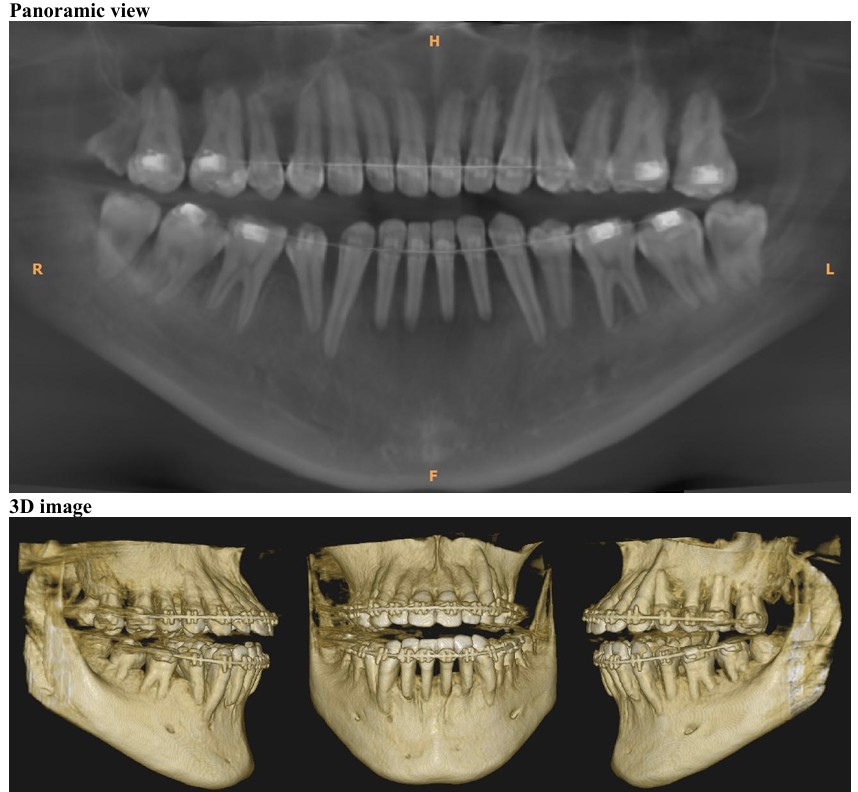

前回1月18日に歯石取りなどを終えており、歯茎の状態も特に悪化していることもなかったので、2月21日にレントゲン検査 (CBCT) 実施後、2月28日と3月28日に歯肉移植手術(下の歯左右2番と3番計4本に対し、左側と右側の2回に分けて行う)を実施することになりました。

・2026年2月21日撮影

・2025年9月13日撮影

・2022年10月1日撮影(約3年前)

レントゲン検査 (CBCT) の結果をもとに、歯肉移植手術を2回(2月28日と3月28日)に分けて実施しました。